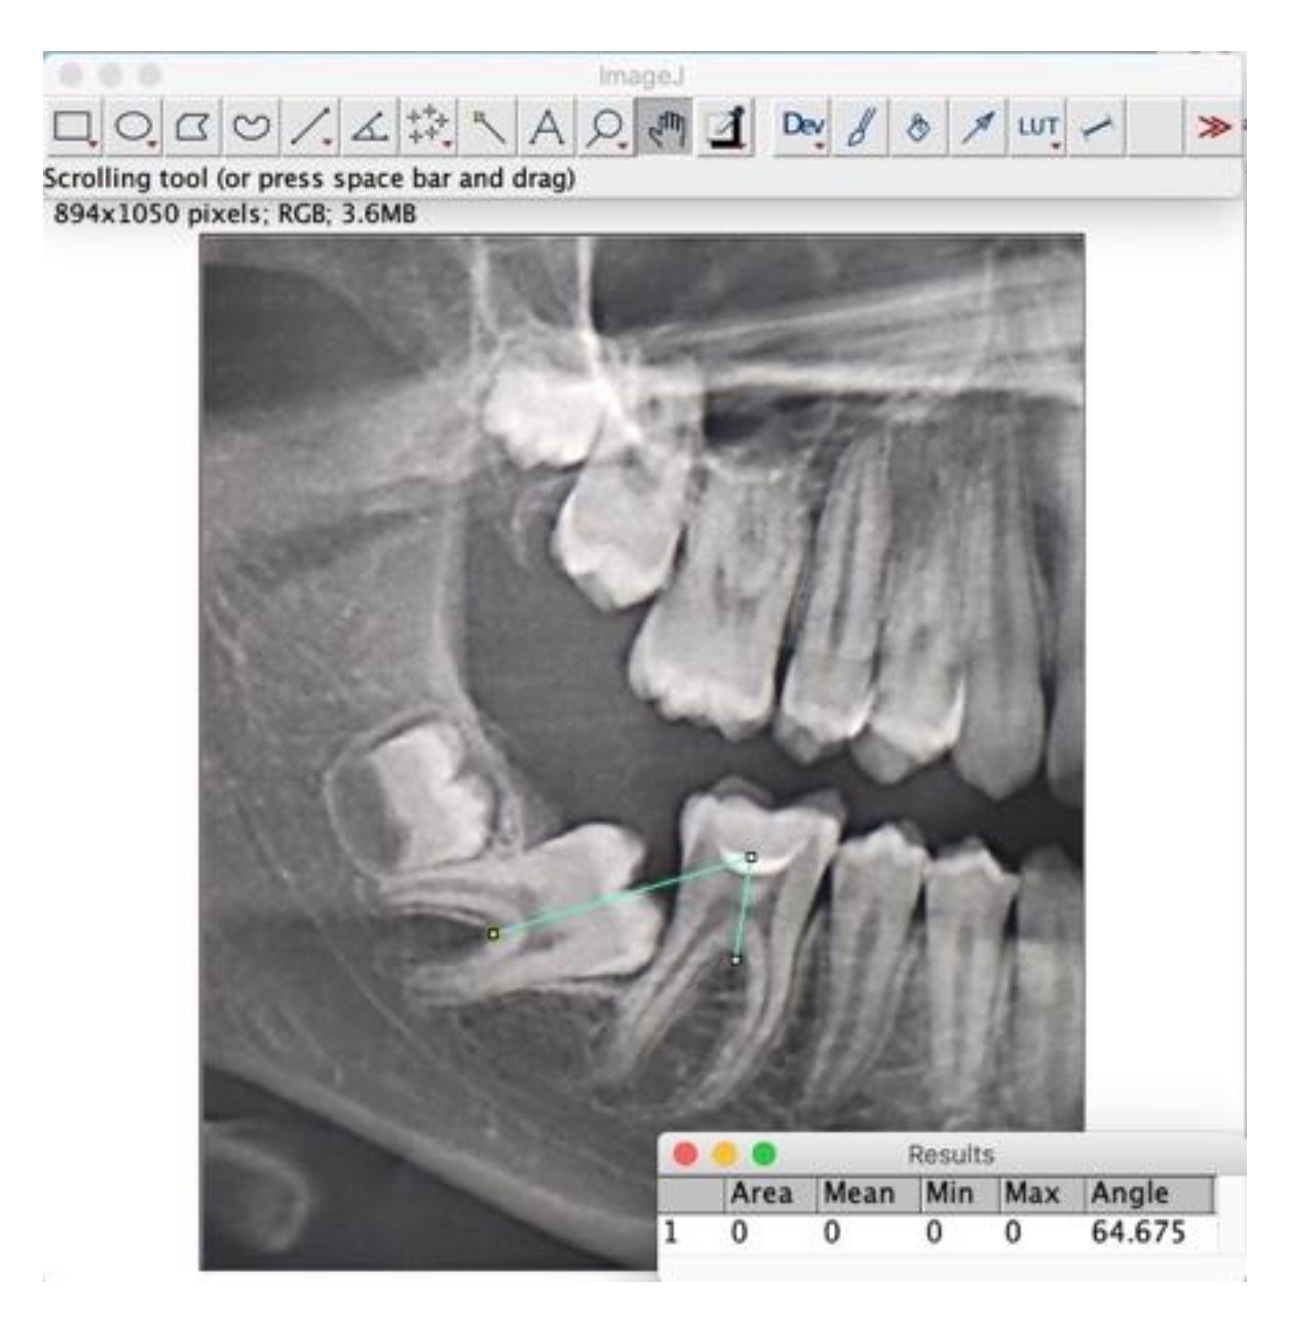

2.3. Measurements

| 8 | 16 | M | 4.7 | intra-osseous | 4.8 | 14 | no | no | 64.6 |